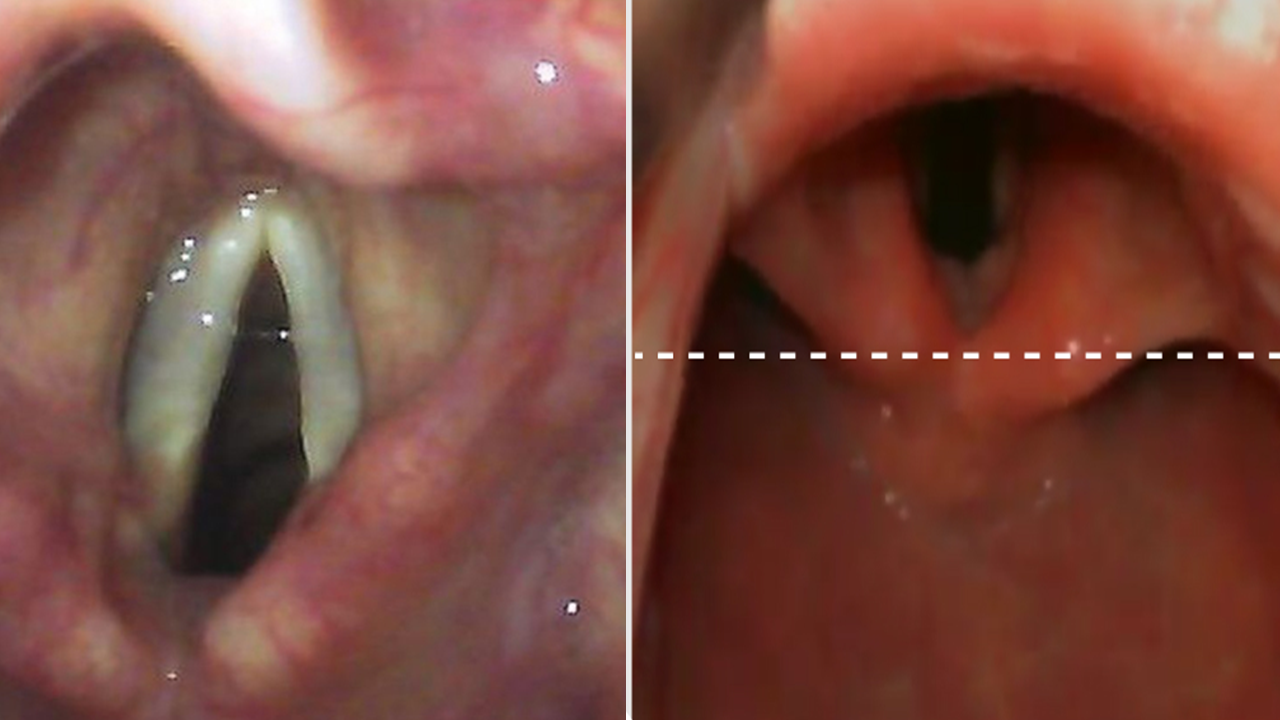

VIA AÉREA DIFÍCIL

AVALIAÇÃO